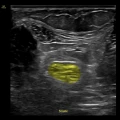

GE Venue è il sistema top di gamma della linea Venue, pensato per il point-of-care.

Con monitor grande da 19″ che facilita la visione da qualsiasi angolo della stanza e supporta esami completi con batteria fino a 4 h, offre imaging clinico chiaro e strumenti automatici basati su intelligenza artificiale per valutazioni rapide e supporto decisionale in ambienti critici, con carrello robusto, gestione intelligente dei cavi e grado di pulizia semplificato per controllo delle infezioni.